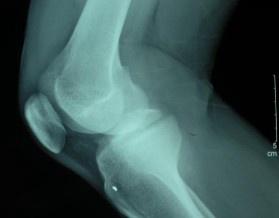

膝關節損傷常見于體育運動中的接觸性或非接觸性損傷,包括膝關節半月板損傷、膝關節韌帶損傷(兩者常合并發生)、髕骨脫位、肌腱斷裂等一系列損傷性疾病。